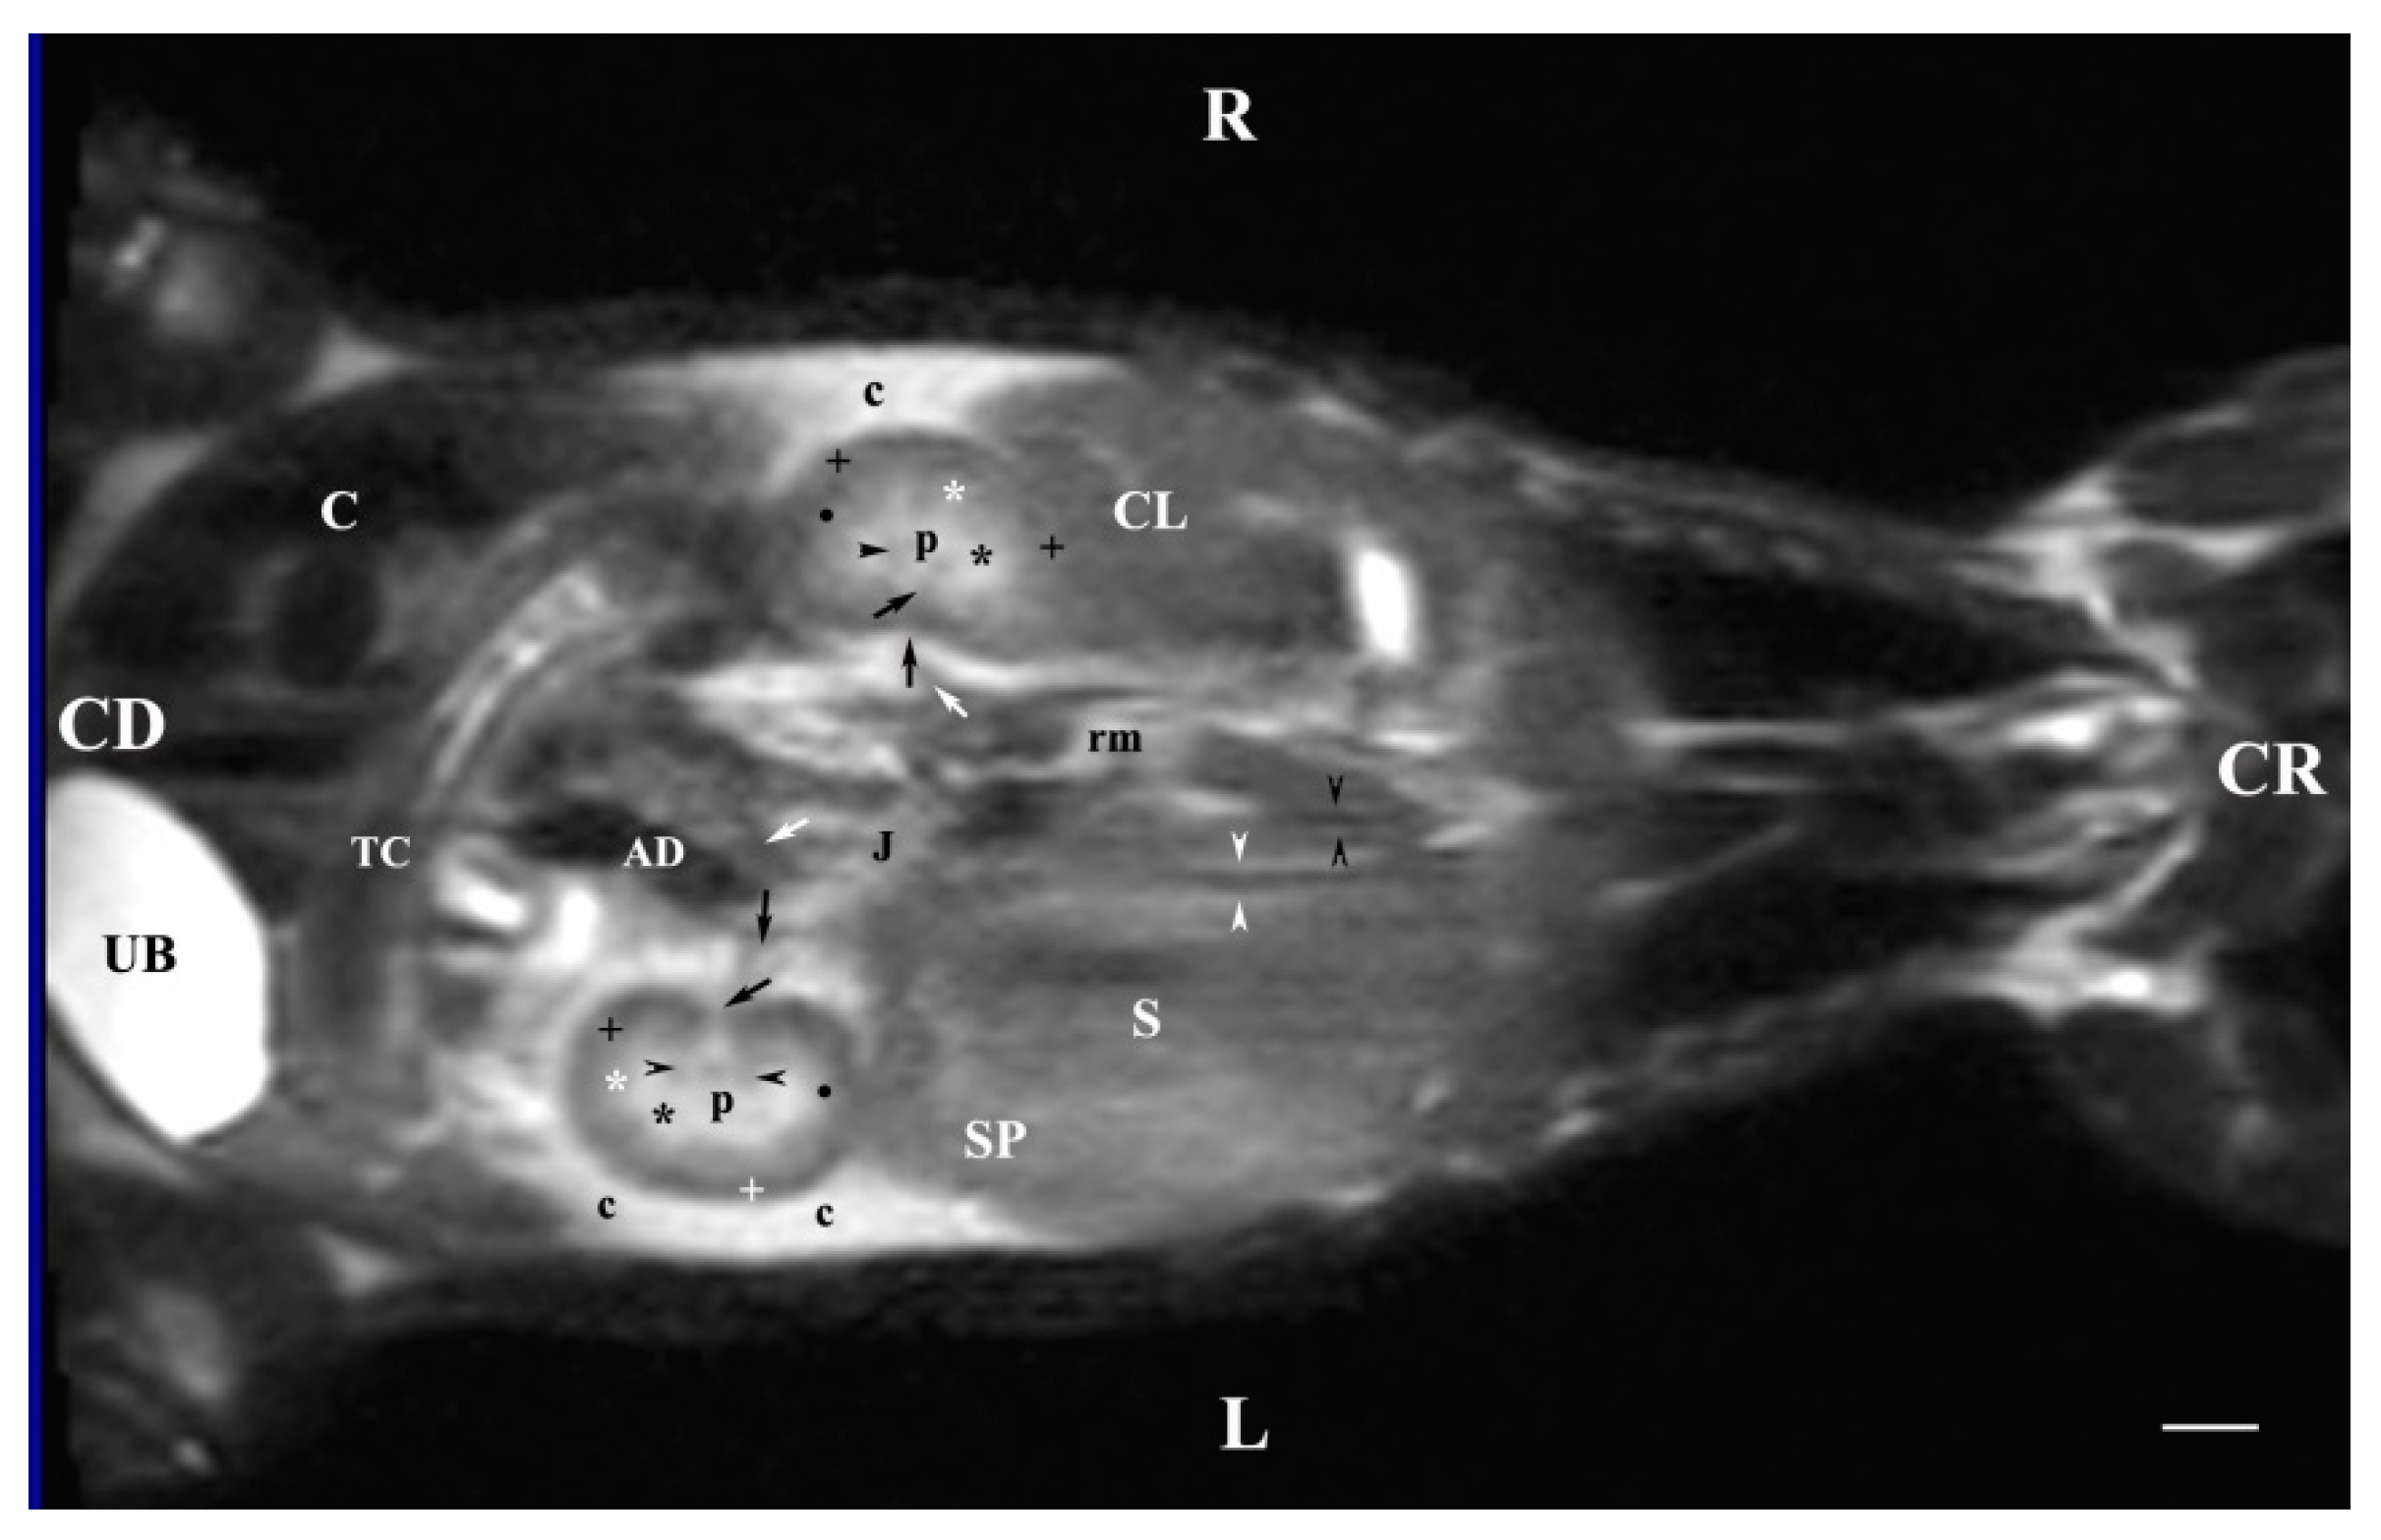

3.3. Dorsal MRI